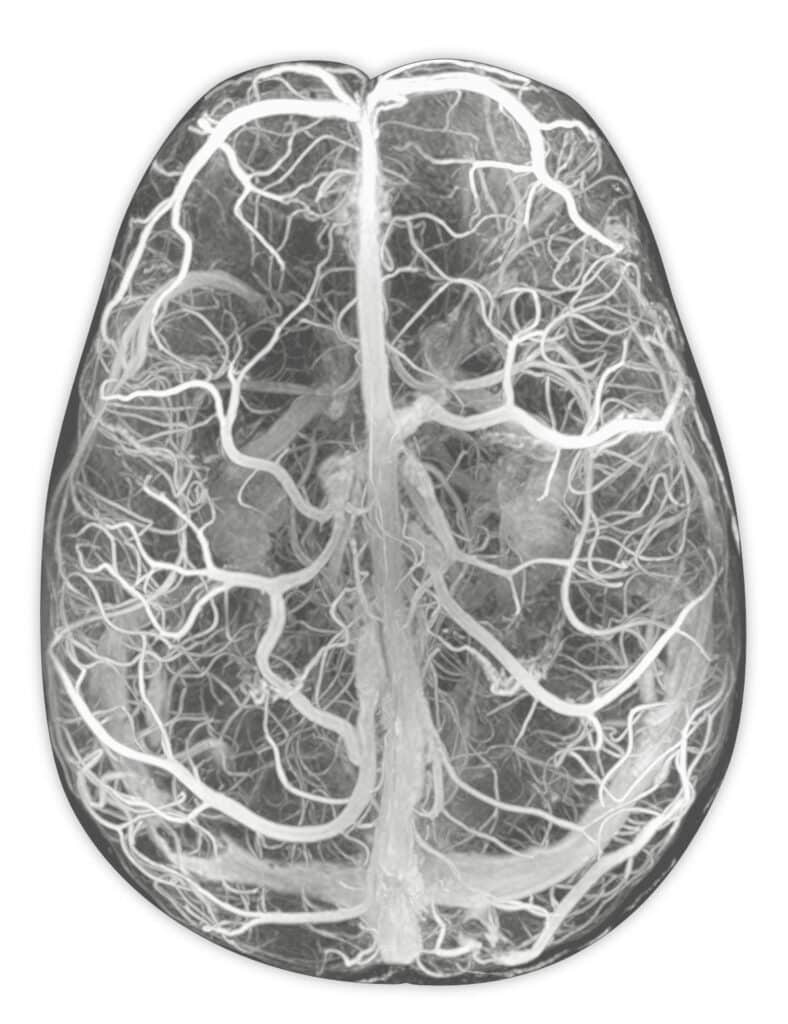

Ressonância dos vasos cerebrais